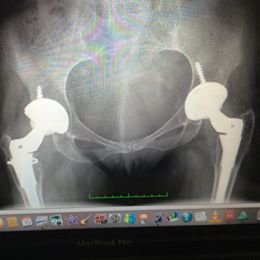

#holisticbodlove Day 1::: When I was 18 I had my left hip replaced (total, ceramic on ceramic: swipe for a rad X-ray), six months later I had the right one replaced.

The scars it has left me with represent the battle I overcame with immense pain, which eventually became so bad it was causing my body to fail and my mind to atrophy.

Every time I see them my heart swells with gratitude that not only was I led to an amazing surgeon, but also that my incredibly stubborn streak helped me navigate the shitty QLD health system (I ended up in Sydney for these babies), & propelled me through the waiting period & the recovery process… it was hard work. I put all of myself into it.

Not only had I survived something which was a bit dicey (I weighed just under 30kg prior surgery, couldn’t eat, couldn’t sleep, lost so much hair, couldn’t string more than two words together), but I now had a future stretched in front of me so different from the one I had previously imagined in my 18 years.

I had better mobility than I had ever known, I could walk like a ‘normal’ person. I had my mental & sensory clarity back, only it seemed much more crisp than ever before.